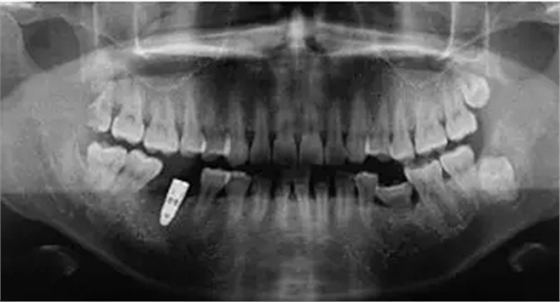

制作放射模板;制備PRF(圖2);微創(chuàng)拔除46后植入PRF(圖3)。3個月后CBCT分析骨質(zhì);行46種植牙修復(fù)術(shù)(圖4)。種植術(shù)后曲面體層片見圖5。病例2應(yīng)用骨粉膠原塞牙槽位點保存后一例基本情況患者男性,47歲。主訴:右下后牙折裂半月。

圖5 種植術(shù)后曲面體層片